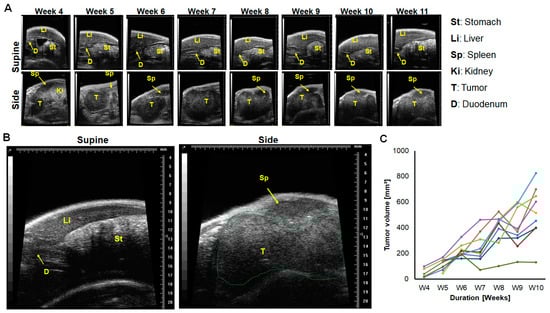

2.1. In a Minor Number of Mice, Implanted Tumors Remained Secluded within the Pancreas, and Almost Outgrew the Pancreas over Time

2.2. Tumor Infiltration of Vital Organs and Disease Progression

- Ultrasound imaging should be carried out preferentially both on the side and supine position in order to monitor the primary tumor and to pinpoint the onset of the infiltration of the omentum and/or stomach wall and metastasis. Furthermore, the use of imaging systems that have higher penetration and/or additionally provide functional and molecular information of the tumors [54] should be considered.

4.4. Monitoring the Orthotopic Pancreatic Tumor Growth by Ultrasound (US) Imaging

| Early | 2–4 weeks | Small tumor secluded in pancreas | No peculiarity | No peculiarity | No peculiarity | Very low <5% oval cells | >20% | −/+ | ≤20% |

| Advanced | 5–7 weeks | Large tumor | Growth towards gastric lobe/omentum | Growth towards gastric lobe/omentum | Omental infiltration | Low, <10% mix of oval/elongated cells | ≥40% | + | ≥40% |

| Late | ≥7 weeks | -Very large tumor -Metastasis in surrounding organs | -Pressure on stomach -Tumor in omentum | -Metastasis in surrounding organs, e.g., spleen | -Pressure on stomach -Omental/or stomach wall infiltration -Metastasis | >10% Mostly elongated | >40% | +++ | > 60% |